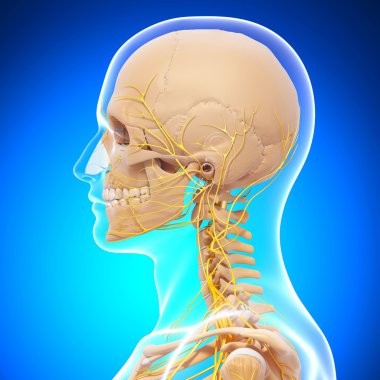

iskelet adam yan görünüm baş ve sinir sistemi

resimlemeİnsanSağlıksağlıklıYaşamkanSağlık hizmetleriTıbbiboğazıçizgi filmsemboldişlerKardiyolojikalpnabızgövdeÇizimbiyolojiBilimbölümgemigerçekçiGöğüsorgBilimselanatomidiyagramPompaGergintedavülarterAtriumApexanatomikSinirlerdolaşımaortkoronerventrikülİnsan Vücududamar sistemiPulmoner fizyolojisiFiziksel bölümdolaşımı kanAnatomi gözlerBenzer İçerikler